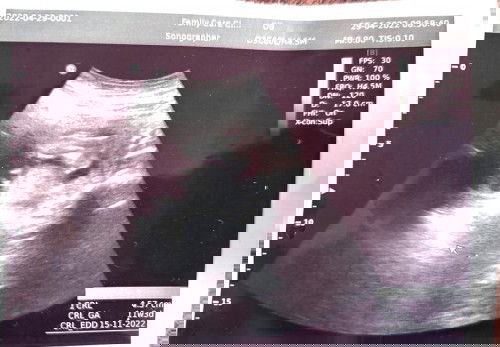

Scan 7W3d, rupanya 11w3d

salam moms,ku sangka 7w3d sekali scan di klinik swasta doc kata 11w3d,di mana silap sy kira ya..😄 kalau nak pegi buka buku klinik kjaan ikut mana?kiraan sy atau ikut kiraan dlm gmbr ne.. #firstbaby #firstmom